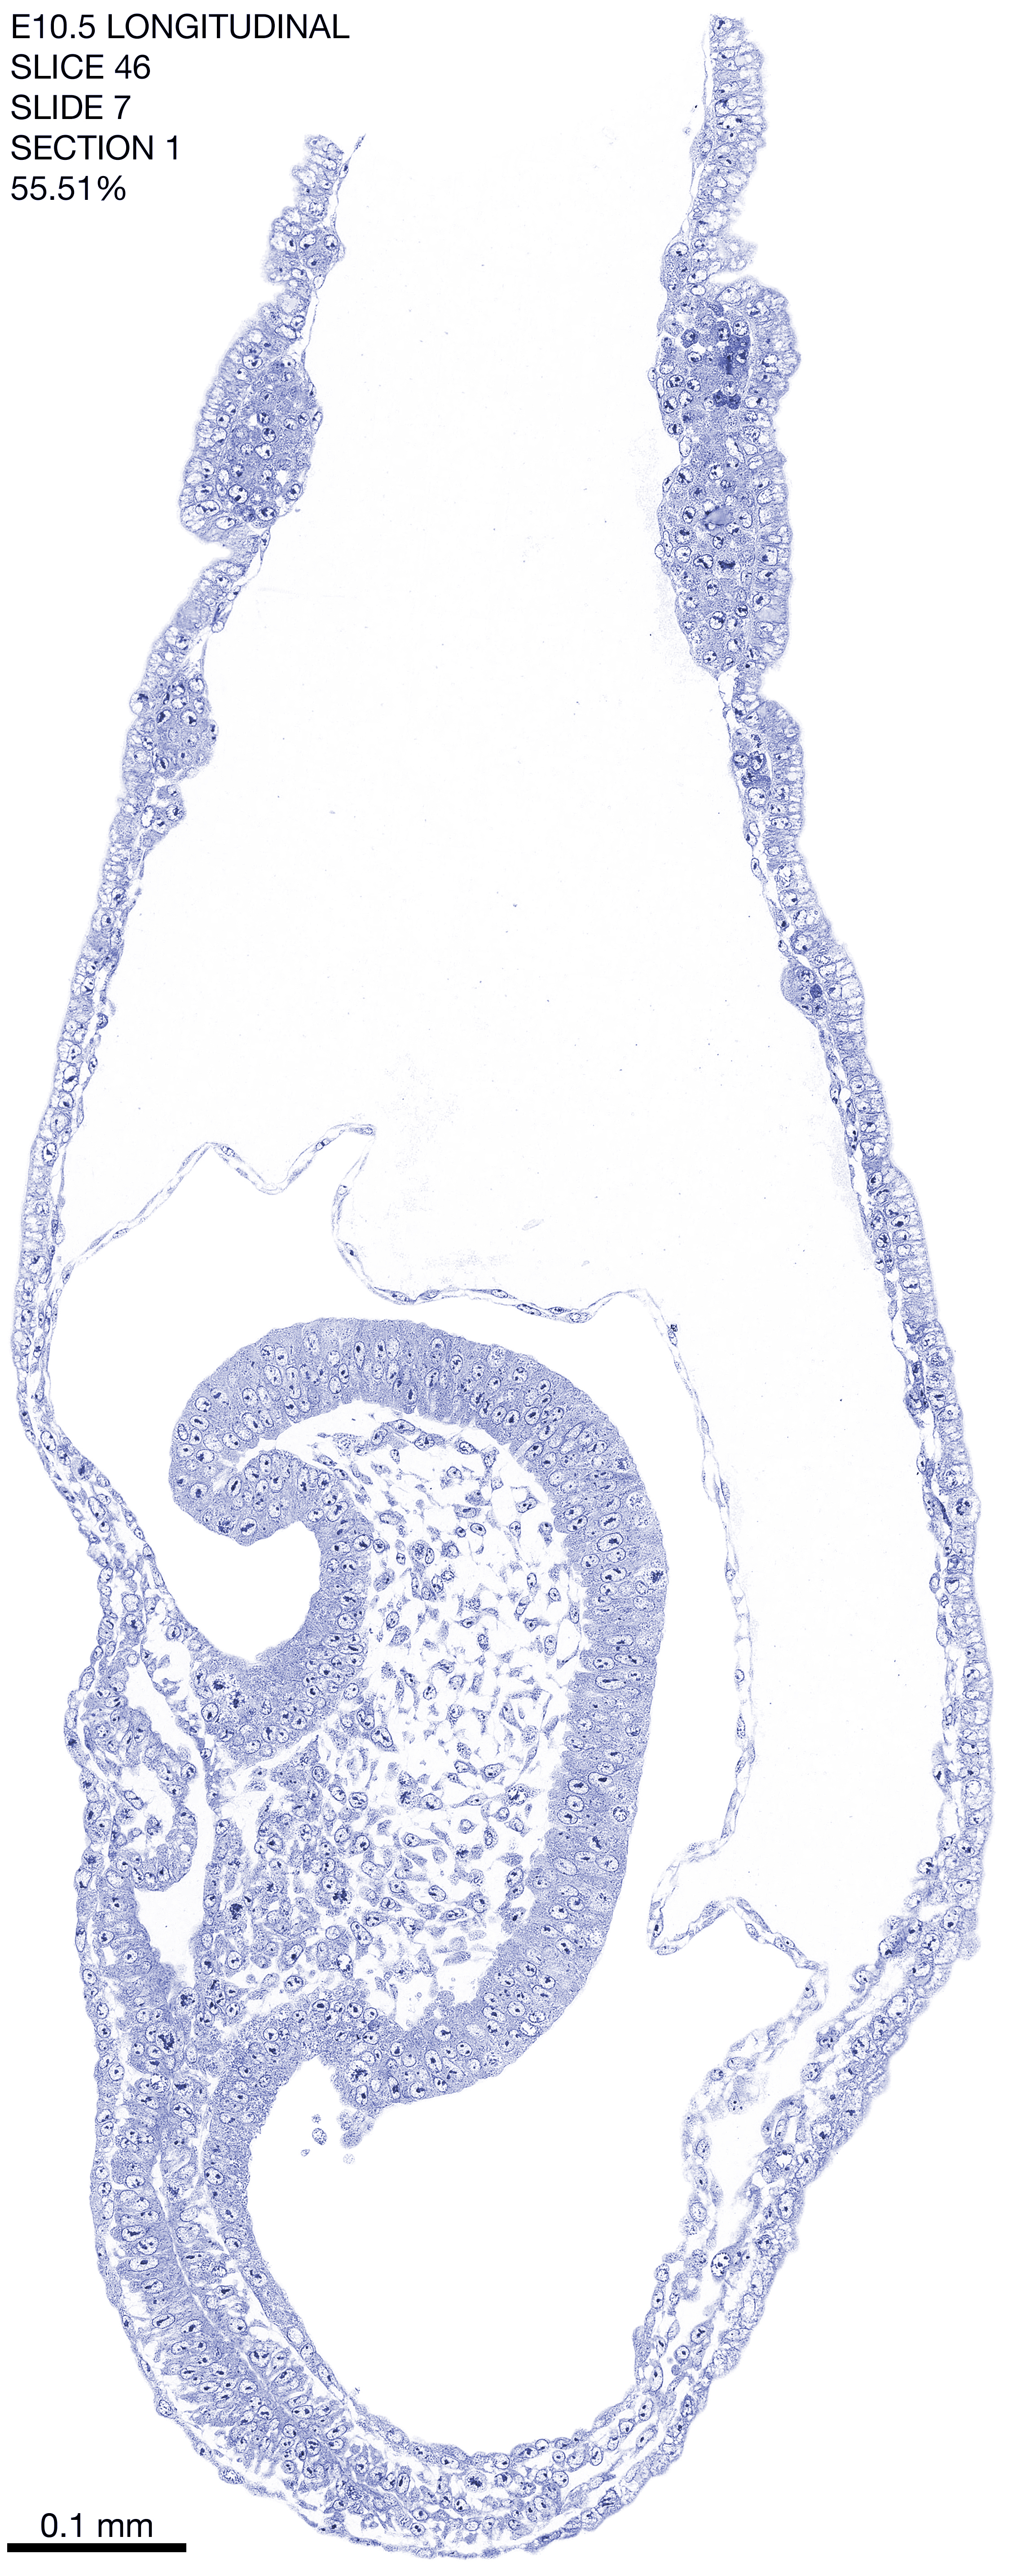

E10.5 Longitudianal Archive This page contains jpg files of ALL SLICES (each 3µm thick) that were scanned of the E10.5 longitudinally cut specimen. Download: Large | High Res Download: Large | High Res Download: Large | High Res Download: Large | High Res Download: Large | High Res Download: Large | High Res Download: Large | High Res Download: Large | High Res Download: Large | High Res Download: Large | High Res Download: Large | High Res Download: Large | High Res Download: Large | High Res Download: Large | High Res Download: Large | High Res Download: Large | High Res Download: Large | High Res Download: Large | High Res Download: Large | High Res Download: Large | High Res Download: Large | High Res Download: Large | High Res Download: Large | High Res Download: Large | High Res Download: Large | High Res Download: Large | High Res Download: Large | High Res Download: Large | High Res Download: Large | High Res Download: Large | High Res Download: Large | High Res Download: Large | High Res Download: Large | High Res Download: Large | High Res Download: Large | High Res Download: Large | High Res Download: Large | High Res Download: Large | High Res Download: Large | High Res Download: Large | High Res Download: Large | High Res Download: Large | High Res Download: Large | High Res Download: Large | High Res Download: Large | High Res Download: Large | High Res Download: Large | High Res Download: Large | High Res Download: Large | High Res Download: Large | High Res Download: Large | High Res Download: Large | High Res Download: Large | High Res Download: Large | High Res Download: Large | High Res Download: Large | High Res Download: Large | High Res Download: Large | High Res